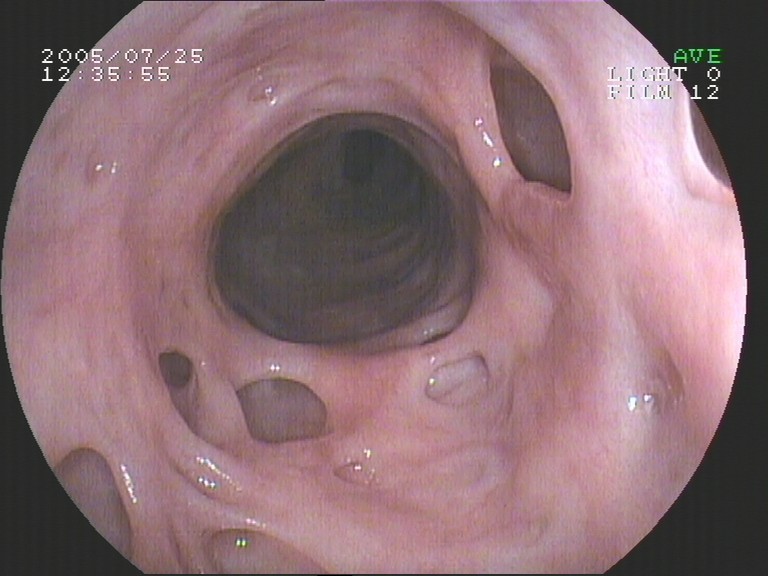

Coloskopie - Divertikulose